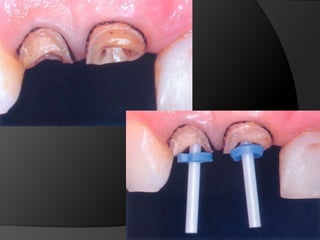

fundamentos de periodoncia en prótesis fijaCuando, por la evolución de lesiones de caries, fracturas, o necesidad de ganancia de retención mecánica en pilares muy cortos, el espacio biológico es violado, existe la necesidad de restablecer sus dimensiones, como una forma de recuperar la salud del periodonto y de facilitar los procedimientos protésicos

fundamentos de periodoncia en prótesis fijaCirugía de Alargamiento CoronalExtrusión OrtodónticaTécnica Combinada